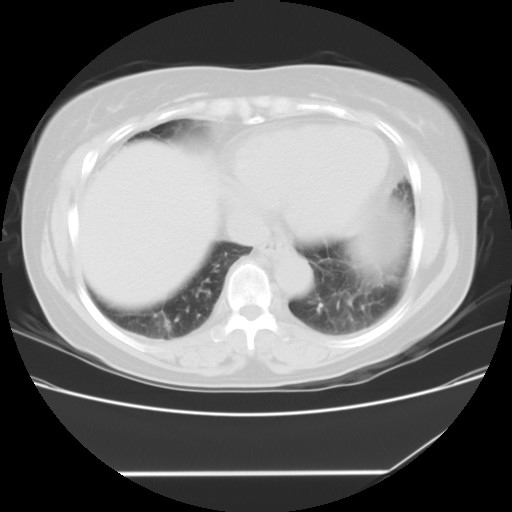

女性,62岁,长期咳嗽,既往从事工作有粉尘接触,有高血压病史,110/150mmhg,近日咳嗽加重,脸面浮肿,请大家帮看下,

1、尘肺;2、慢性支气管炎合并肺部感染;3、心影增大(左房、左室大),考虑高血压性心脏病。

慢支并肺部炎症;右肺结核球?主肺动脉、右肺动脉影不宽,右心室不大,不支持肺心病;无心包积液。

间质性肺炎,有纤维化趋势。

1)慢性支气管炎并肺部感染、肺气肿。2)肺间质纤维化。

间质性肺炎,左下肺机化性肺炎。